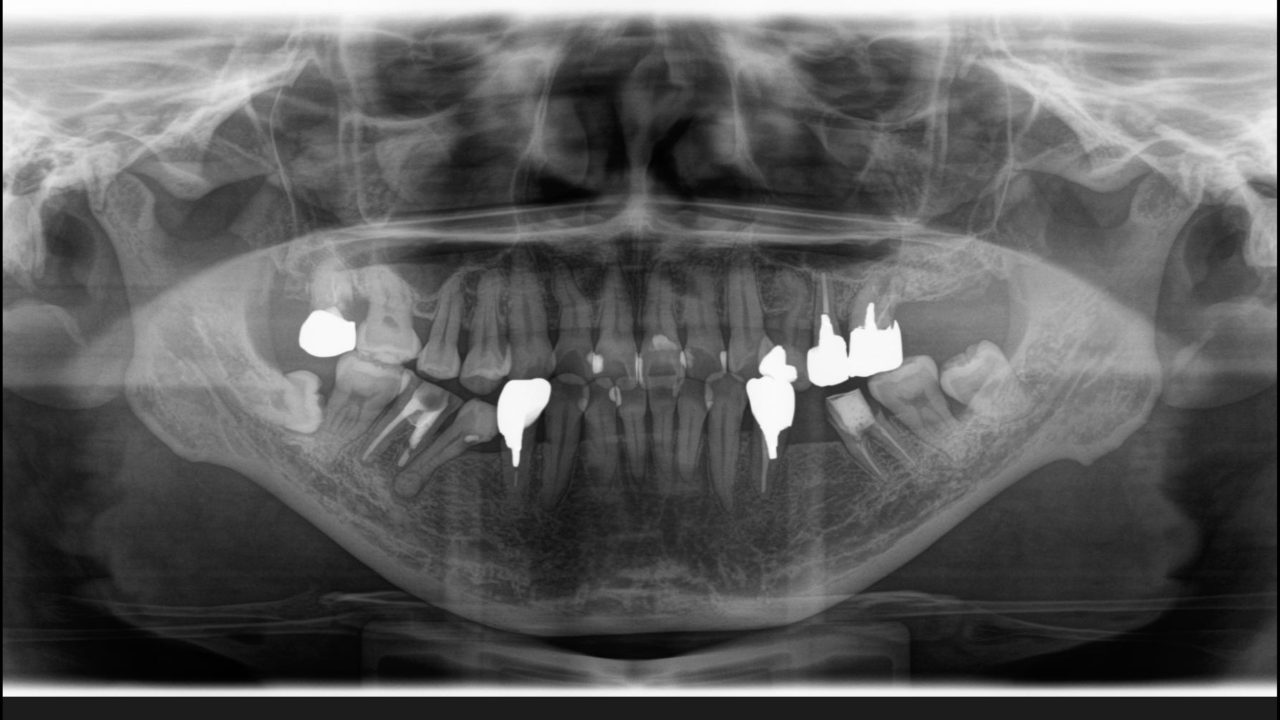

初診 レントゲン